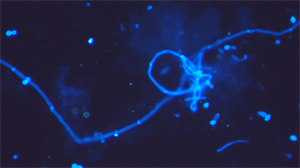

广西自贸区医院于2025年引入广州明慧公司UB203i-FL荧光显微镜,专用于真菌荧光染色观察,解决了传统染色方法灵敏度低、成像模糊的难题。该设备通过高亮度荧光照明系统和精密滤光片技术,确保激发光线精准匹配真菌特异染料,显著提升图像分辨率与对比度,使细长病原体结构在显微镜下清晰可见,有效减少漏诊风险。

精准成像优化诊断:UB203i-FL专为真菌荧光设计,通过紫外(330-385nm)、蓝色(450-490nm)等多波段激发光系统,精确分离荧光信号,捕获细胞壁特征,成像效果满足临床微生物荧光检测要求。